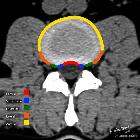

Disc protrusions are a type of disc herniation characterized by protrusion of disc content beyond the normal confines of the intervertebral disc, over a segment less than 25% of the circumference of the disc. The width of the base is wider than the largest diameter of the disc material which projects beyond the normal disc margins. The protrusion must not extend above or below the relevant vertebral endplates .

A disc protrusion is also described in terms of its axial position, into central, subarticular, foraminal, extraforaminal, or anterior locations .